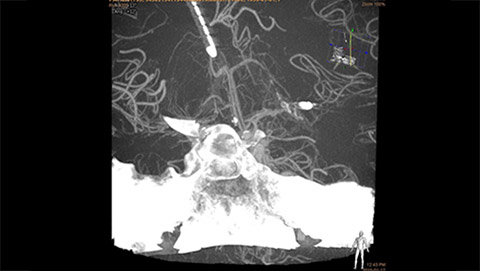

MR/CT Roadmap visualizes lesion boundaries and corresponding vascularization, while helping you to manage X-ray dose and contrast medium. 3D Roadmap provides full 3D view for dynamic guidance of guidewire and catheter navigation through complex vascular lesions.

2D navigation with Roadmap Pro is supported by automatic, real-time motion compensation and decreased subtraction artifacts. Clinical modes are optimized for various clinical applications.